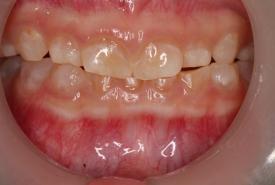

Comprehensive Dental Rehabilitation of an Osteogenesis Imperfecta Child with Dentinogenesis Imperfecta Type 1